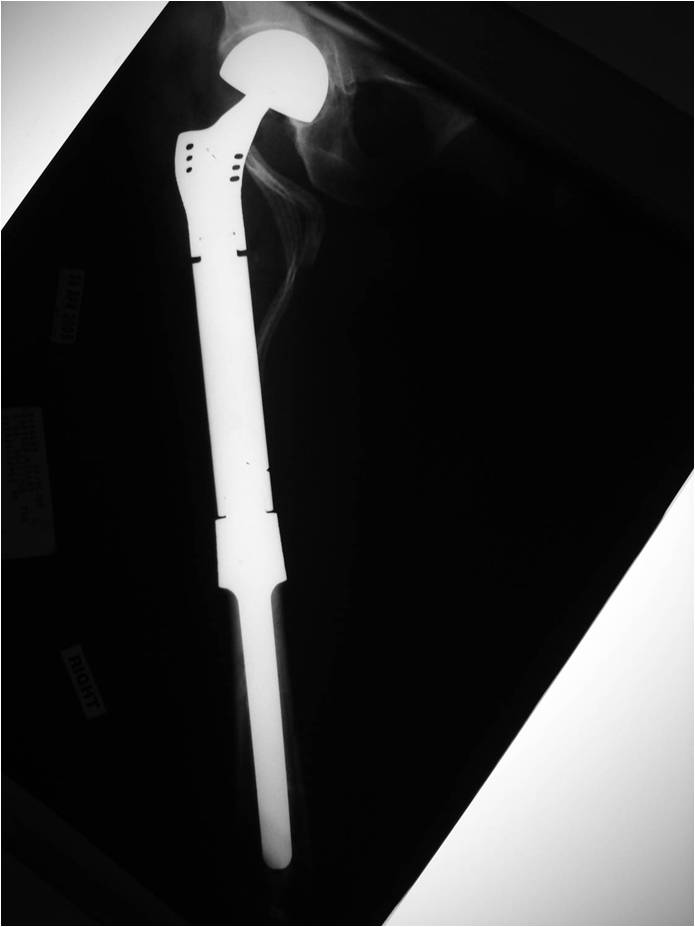

Radiology emulates pathology: Biphasic Tumor

- One region low grade chondrosarcoma

- Second more aggressive area with bone destruction, lysis of calcification, soft tissue mass

- Cortical permeation and a soft tissue mass in 70% of cases

Characteristically abrupt transition between chondroid tumor and dedifferentiated, lytic component

Bone may be expanded and adjacent cortex thickened

(Right Arrow)Aggressive Lytic Area (Dedifferentiated Sarcomatous Component) Cortical Destruction Soft Tissue Mass without Calcification

- Wide/Radical limb sparing resection whenever feasible

- Amputation may be necessary for large tumors